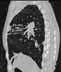

¥ Secondary bronchiectasis

1mmx4, Pitch 3.5, 39 seconds